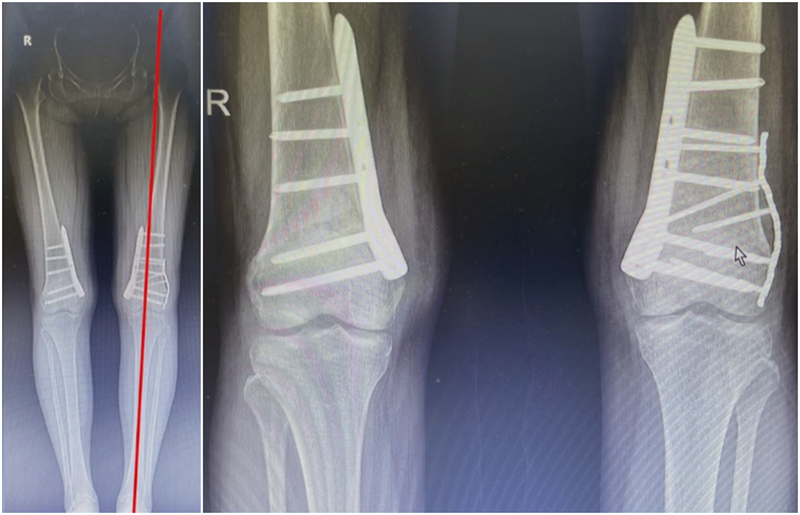

病例,X患者,女,双侧外翻膝,行双侧DFO。

术后6周摔伤,一侧出现膝内翻。

影像学检查显示左侧出现合页断裂。

进行翻修,术前力线显示内翻。